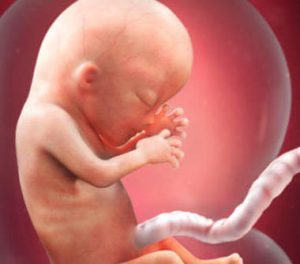

Começa um novo trimestre e outra fase do processo de gestação dessa pequena criatura que vive em seu útero. Na 13ª semana da gestação, o tamanho do feto está entre 6,5 e 10 centímetros e seu peso varia de 12 a 13 gramas. Seu rosto começa a adquirir traços peculiares, entre outras transformações que detalharemos a seguir. É incrivelmente emocionante!

Além da localização definitiva dos olhos (que no começo estavam muito separados um do outro) e das orelhas, que desde a semana anterior se posicionaram onde vão permanecer por toda a vida (costumavam ficar mais atrás), existe um detalhe realmente fascinante: as impressões digitais já estão presentes.

Como o cérebro é uma das partes mais desenvolvidas do feto, além das estruturas que sustentam e revestem os órgãos, nesse momento a cabeça corresponde à metade do tamanho total do feto.

A partir desse momento, o corpo vai começar a crescer de forma mais acelerada para “alcançar” a cabeça e conseguir, assim, um corpo proporcional. Na verdade, no momento do nascimento, a cabeça representa apenas um quarto do tamanho total. Além disso, também acontecem nessa fase dois processos importantíssimos relativos ao organismo do feto e seu funcionamento.